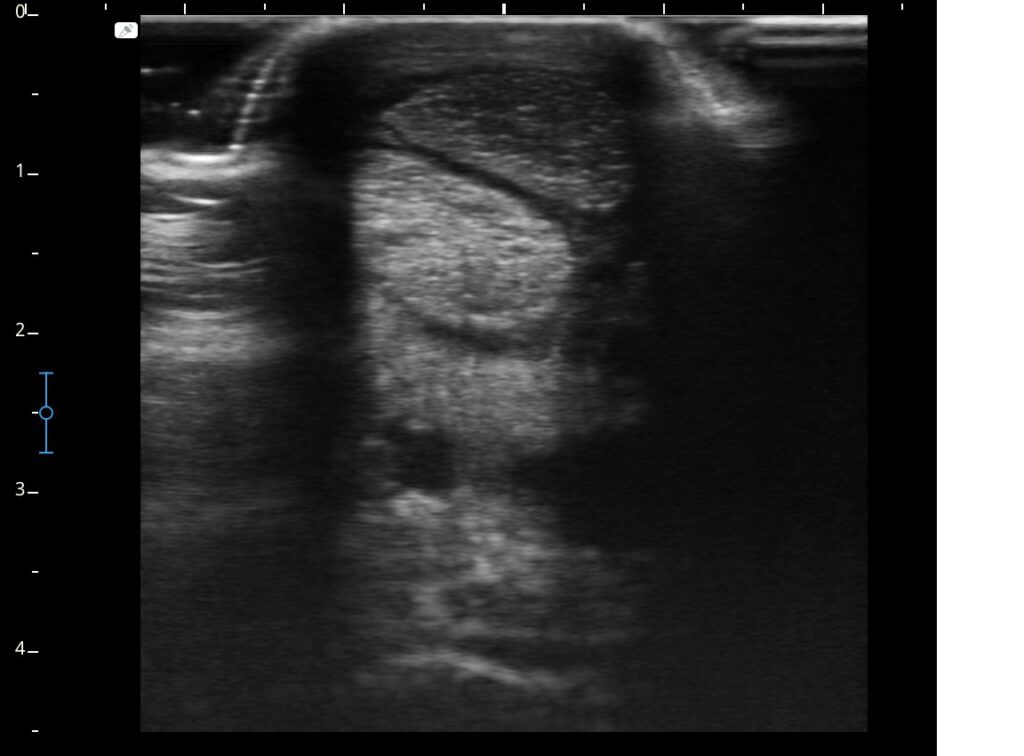

Ultraschall, Röntgen